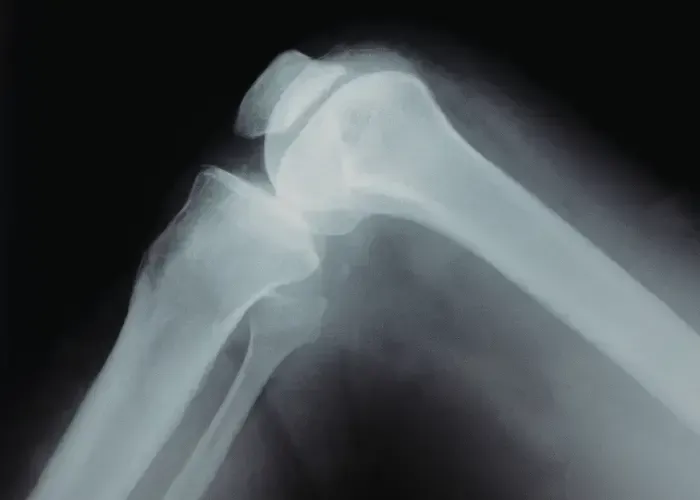

The result is pain (sometimes severe) and limited mobility. Understanding the syndrome means understanding the mechanics of the knee joint. The thighbone (femur) and lower leg (tibia and fibula) are joined by the knee, a large, complex hinge. A groove runs along the front of the joint, where the thighbone ends.

The patella sits in the groove and is held in place by a network on the sides by ligaments and at the top and bottom by tendons. The underside of the kneecap is a layer of cartilage that allows it to move easily, or glide, along the groove. When there is a problem with any of the parts that make up the knee it can lead to patellofemoral tracking syndrome.